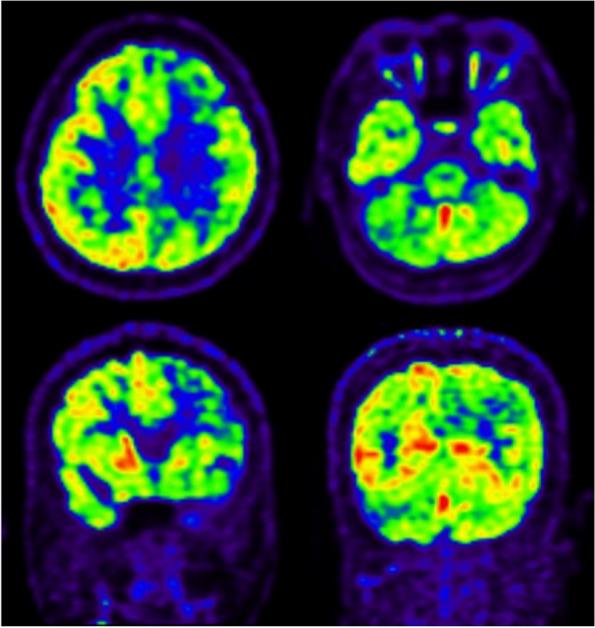

Approximately 58 subjects with disease-causing variants of FARS2 have been reported, including 31 cases of early onset epileptic encephalopathy, 16 cases of hereditary spastic paraplegia, 3 cases of juvenile-onset epilepsy, and 8 cases of unknown phenotype. We report a case of autosomal recessive COXPD14 in an adult with status epilepticus as the only manifestation with a good prognosis, which is different from that in neonatal or infant patients reported in the literature. c.467C > T (p.T156M) has been previously reported, while c.119_120del (p.E40Vfs*87) is novel, and, both mutations are pathogenic.

This case of autosomal recessive COXPD14 in an adult only presented as status epilepticus, which is different from the patients reported previously. Our study expands the mutation spectrum of FARS2, and we tended to define the phenotypes based on the clinical manifestation rather than the age of onset.